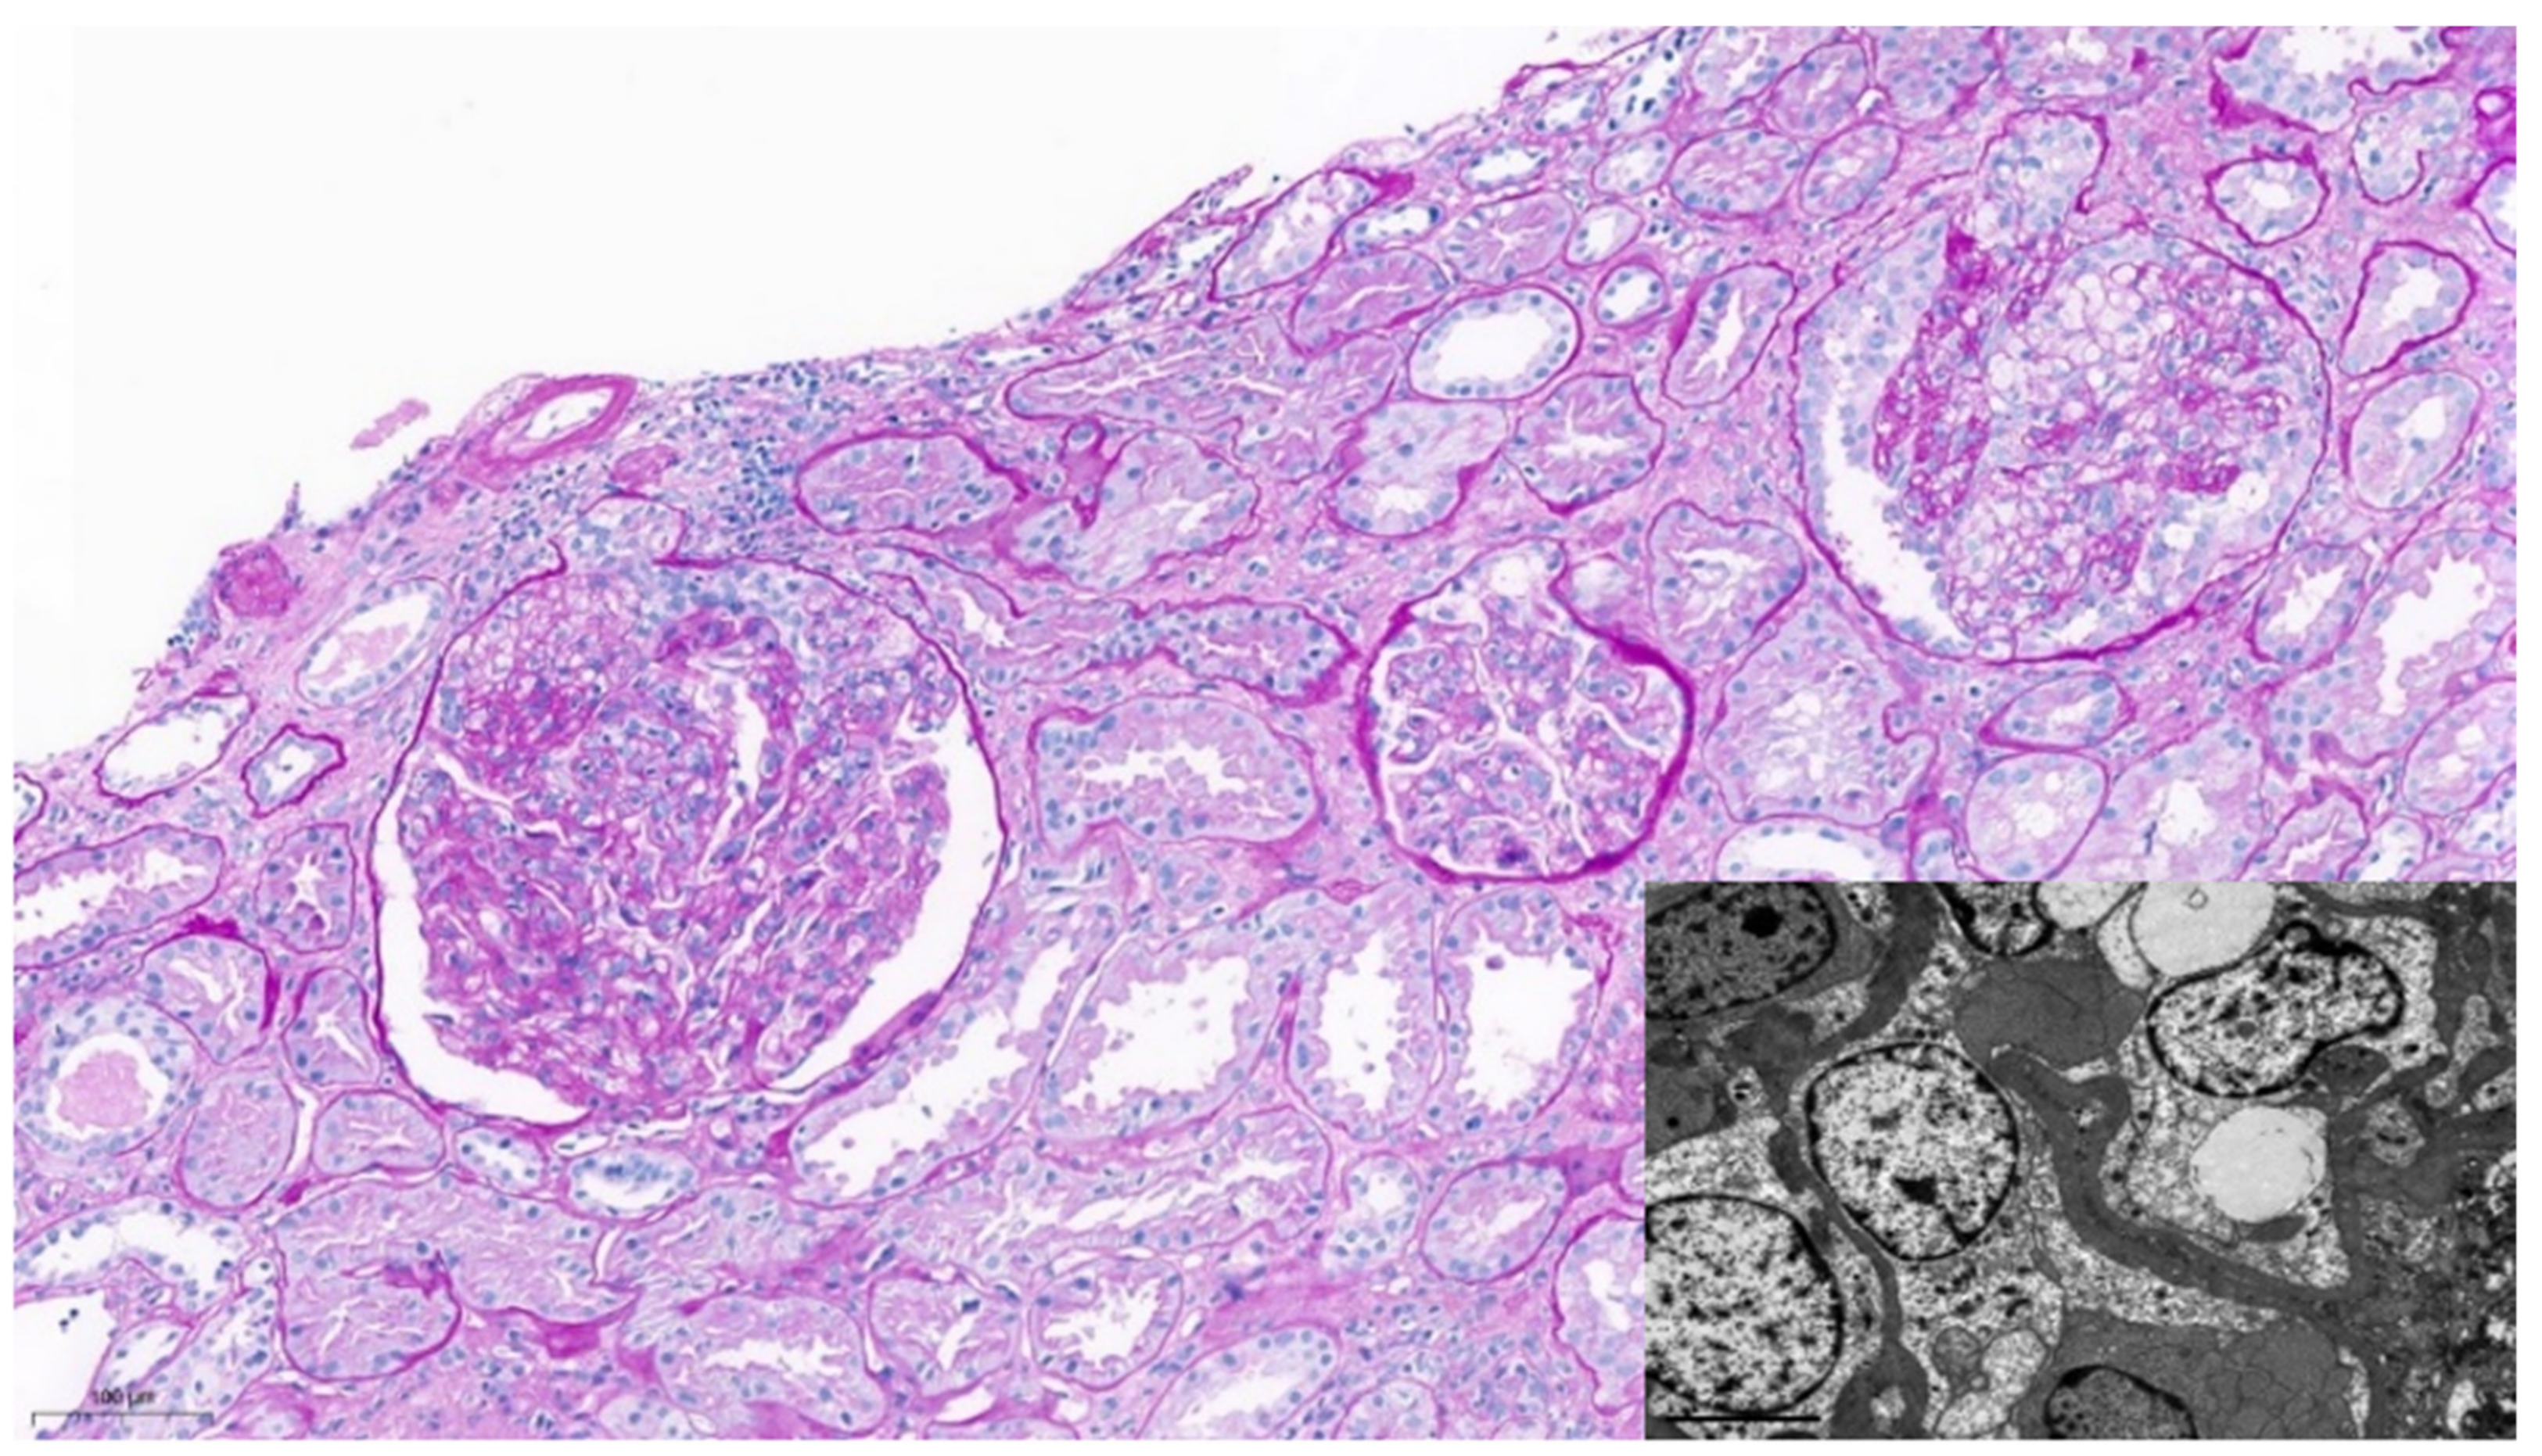

The patient received the vaccine for SARS-CoV-2, mRNA-1273, with the first dose on 25 March 2021 and the second dose on 22 April 2021. Ten days after the first dose, he reported the appearance of lower limb oedema, that increased significantly after the second dose. The next day, a urinary dipstick showed high grade proteinuria and the patient promptly contacted our renal transplant unit. On 11 May 2021 we confirmed a nephrotic range proteinuria of 7810 mg/d, with mild creatinine elevation of 120 umol/L, eGFR of 59 mL/min, with plasma albumin in the low limit of 37 g/L and low total proteins of 58 g/L. He had reduced serum IgG (6773 mg/L). He showed indetectable BK, CMV and EBV PCR in blood. DSA were negative. The urine sediment did not show microhematuria. Due to severe nephrotic syndrome, with a proteinuria rising to 13,450 mg/d, a kidney biopsy was performed (Figure 1).

A total of 37 glomeruli were identified, two of which were globally sclerotic. Many of them showed segmental endocapillary hypercellularity occluding lumens and focal foamy macrophage infiltration. In those glomeruli, epithelial hypertrophy and hyperplasia in the Bowman space was seen. Intact portions of the glomeruli showed minimal mesangial expansion, and in other glomeruli collapse of the basement membrane was prominent. Focal acute tubular necrosis was the most relevant finding in the interstitial compartment.

Direct immunofluorescence evaluation was negative in the glomeruli. Additionally, C4d was negative in the peritubular capillaries.

Ultrastructural examination revealed extensive foot process effacement and segmental hypertrophied podocytes. No immune-type electron dense deposits were identified.

Figure 1. Periodic acid–Schiff stain x13: Endocapillary hypercellularity with epithelial hypertrophy in two glomeruli and segmental foam cells infiltration (top right). Basement membrane collapse. No necrotizing lesions were present. The interstitium shows mild focal infiltrates predominantly consisting of lymphocytes and plasma cells. No tubulitis, capillaritis or endothelialitis are present. The degree of interstitial fibrosis and tubular atrophy is mild. Electron microscopy: Extensive foot process effacement and segmental hypertrophied podocytes (lower left). Although some of the findings are consistent with the cellular variant, this image is, according to the Columbia classification, a Collapsing Glomerulopathy.